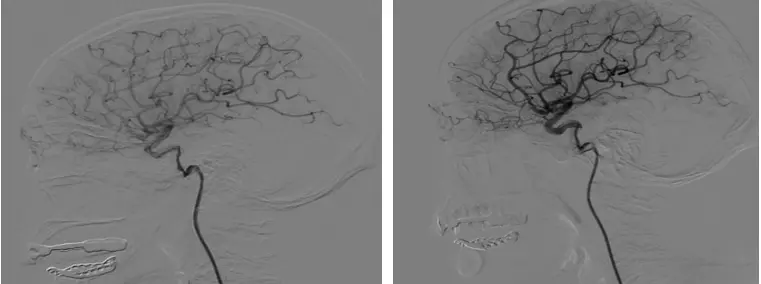

窦晓燕主任马上给予吸氧、眼球按摩、降低眼压治疗,症状无明显改善,立即和我院神经外科伍健明团队联系,急转入神经外科救治,何毅主任医师查看病人后认为,患者左眼视网膜中央动脉阻塞虽然有约8个小时,仍然有溶栓适应症,无溶栓禁忌症,启动绿色通道,即刻行经导管颅内血管血栓去除术治疗。目前患者蒋先生视力恢复良好,正在行高压氧治疗。

(2)眼底镜检查发现视网膜水肿、樱桃红色斑点、减弱的视网膜动脉中节段性血流缓慢、视神经盘无异常。成像方式如光学相干断层扫描、光学相干断层血管造影或荧光素血管造影均可支持CRAO诊 断。同时应注意筛 查有无视网膜动脉栓子和血管炎症。